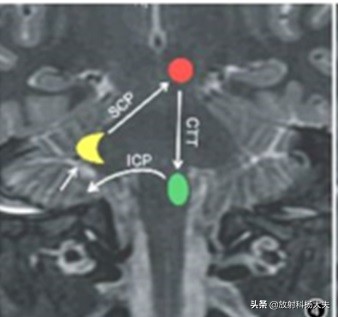

如上图所示,这个三角是由三个神经核(中脑红核-红色圆形、延髓下橄榄核-绿色椭圆和对侧的小脑齿状核-黄色月牙)作为顶点,神经核间的神经纤维束作为三角形的边构成的神经元环路。

红核经被盖中央束(CTT)将信号传递至同侧下橄榄核,下橄榄核先发出纤维经对侧小脑下脚(ICP)进入对侧小脑皮质浦肯野细胞,再由小脑皮质投射到对侧齿状核,小脑齿状核的信号经小脑上脚(SCP)神经纤维传递回到红核,形成环路。我们可以注意到下橄榄核与对侧齿状核不是直接连接。